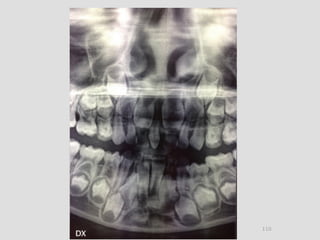

Panoramic (reconstructed from CT)

The most likely diagnosis for the facial asymmetry of this young girl is an

undiagnosed condylar fracture that most likely happen when she falled on a meta

crossbar bar ladder 2 or 3 years ago while she was 4 - 5 years old or so. The

condylar stump has healed and a new condylar head has formed, but the losted

substance of the condyle is gone. Therfore, the height of the ramus has

shortened.

The left ramus and condylar neck are shorter and the left eminence has no slope

if any. Healing and normal growth had reshaped both condyle and eminence.

!

Read more

When looking to the condyle from an anterior view, one can see the oblong

shape of a condyle but the left condyle is smaller.

The midline are not coincident. Note that the lower midline is toward right like

the occlusal plane canting to the right. This can be explained by the lack of

heigh of the left ramus and as normal growth occur, there is a wagon wheel

effect and the midline deviate toward the normal side, the occlusal plane is

moving up on the affected side.